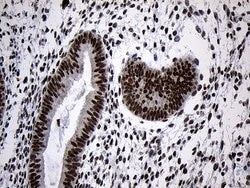

ZNF670 Monoclonal Antibody for Western Blot, IHC (P)

| Immunohistochemistry (Paraffin), Western Blot | |